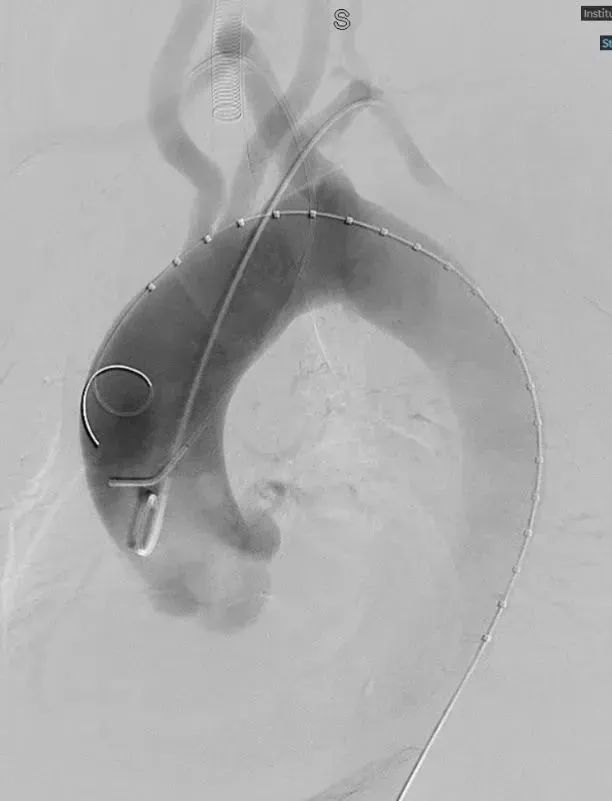

置入覆膜大支架;

右锁骨下动脉置入Viabahn和Smart Control支架(烟囱);

左侧置入Viabahn支架(烟囱);

术后造影复查,右侧迷走锁骨下动脉的烟囱支架角度平顺,血流通畅。

术后随访:

6个月后再次随访,CTA影像图显示血管形态良好,血管支架通畅。